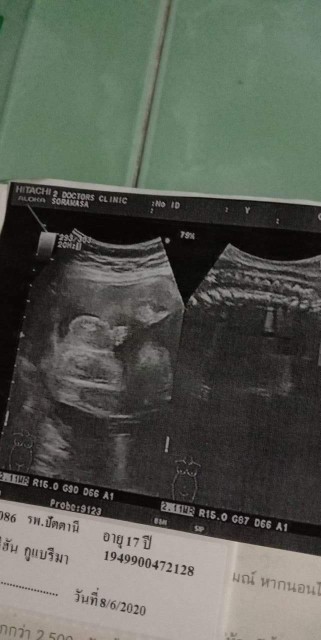

āđāļāđāļāļāļđ āļŦāļĨāļāļĨāļđāļ #āļāļāļāļđāđāļāļāļēāļ§āļāđāļāļĩāļĄāļāļļāļĨāļēāļŦāļāđāļāļĒāļāđāļ° ðĨ°ð§ļ